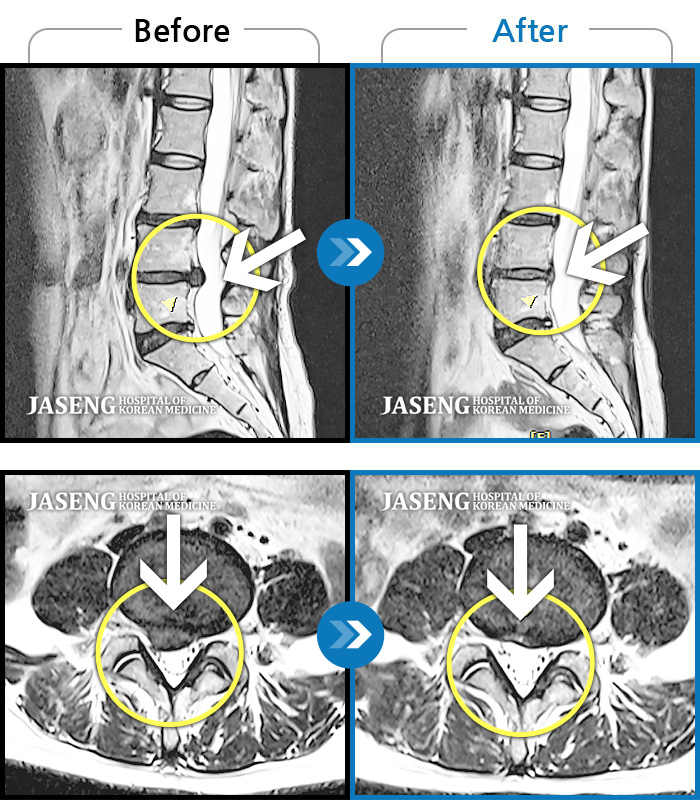

허리디스크

광주 · 김동은 원장

좌측 골반 및 종아리부터 발까지 이어지는 저림과 통증으로 내원하셨습니다.

촬영시기

2023.10.03 ~ 2025.08.14

2025.08.22